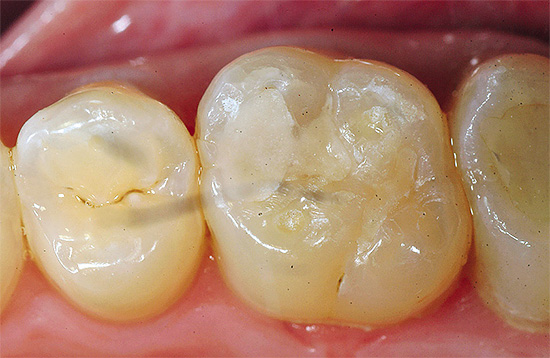

Infelizmente, nem tudo depende da própria pessoa. Há outro fator importante que algumas pessoas encontram ao lidar com um dente problemático: a ocorrência secundária de cárie em um recheio no caso de várias violações nele ou embaixo. Se algumas etapas do tratamento de cárie profunda por várias razões foram realizadas com um erro, a cárie profunda ocorre sob o selo. Isto é especialmente verdade para defeitos e lascas de vedantes mal colocados.

- Com uma cavidade cariada mal limpa da dentina infectada e amolecida, quando o preenchimento não pode ficar elementar nos tecidos moles do dente.

- Com mau isolamento da área de trabalho da saliva, líquido gengival e sangue. Frequentemente, durante o trabalho, os meios necessários de isolamento e preparação para o preenchimento não são utilizados, e a maioria dos materiais para o preenchimento, como você sabe, não é suficientemente firme em um ambiente úmido. Com resultados a longo prazo, isso leva à perda de todo ou parte do selo, lascas, rachaduras, violações do ajuste marginal, etc. De qualquer forma, o processo de cárie dentária geralmente continua após esse tratamento.

- Violando as instruções para o material de enchimento selecionado ou com a escolha incorreta do material em uma situação clínica específica. Devido à variedade de recheios modernos, são possíveis erros na fase de definição do material, geralmente associados ao prazo do médico. Qualquer ninharia para recheios "leves" modernos é especialmente importante e determina sua garantia e durabilidade.